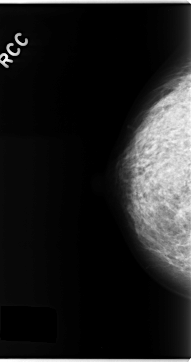

C_0153_1.RIGHT_CC

RIGHT_CC LINES 4696 PIXELS_PER_LINE 2480 BITS_PER_PIXEL 12 RESOLUTION 50 NON_OVERLAY